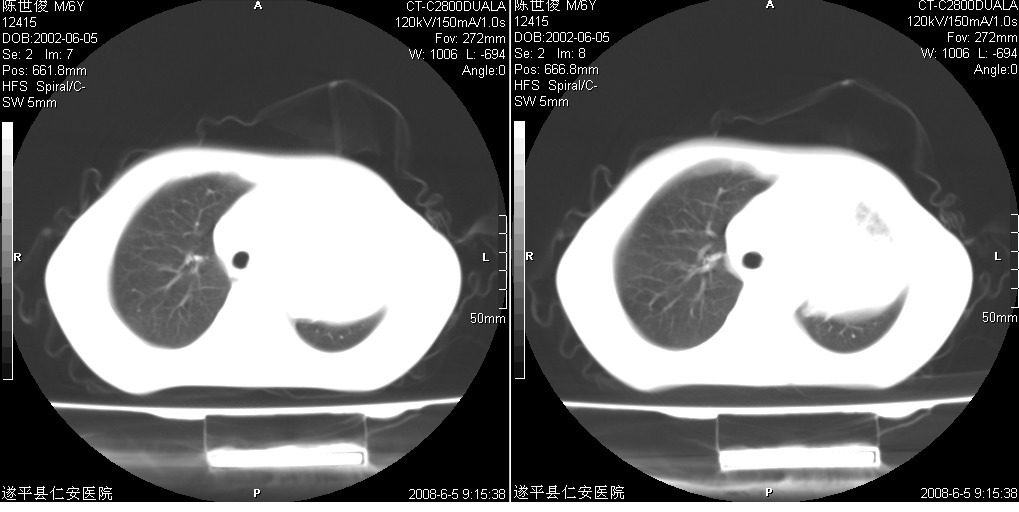

以下是引用xxhwh在2008-6-10 18:40:00的发言:[br]男,6岁,无规则发热一月余,体温在37.8——39度之间。一月前拍胸片示左上肺密度增高影,进行抗炎治疗8天,复查胸片未明显吸收。又改变抗菌素继续治疗半月,照胸片示病灶吸收不明显,行ct检查[br]征象:左上肺前段呈密实影,内可见支气管气像,远侧见絮状模糊影,中上纵隔左移。[br]意见:左上肺前段膨胀不全及感染,考虑为支气管异物或支气管内膜结核所致,[br]建议追问有无异物吸入史,行痰检及ppd检查